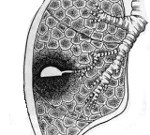

Патоморфологическую основу хронического абсцесса легкого составляют необратимые изменениям в легочной ткани. Стенка гнойника утолщена, представлена грубой фиброзной тканью. Каждое обострение инфекционного процесса ведет к распространению пневмосклероза в окружности абсцесса, деформации бронхов, тромбозу сосудов. Бронхогенное распространение инфекции обусловливает образование новых гнойников в легком. Аррозия стенки бронхиальных артерий может приводить к профузному легочному кровотечению, часто заканчивающемуся фатально.